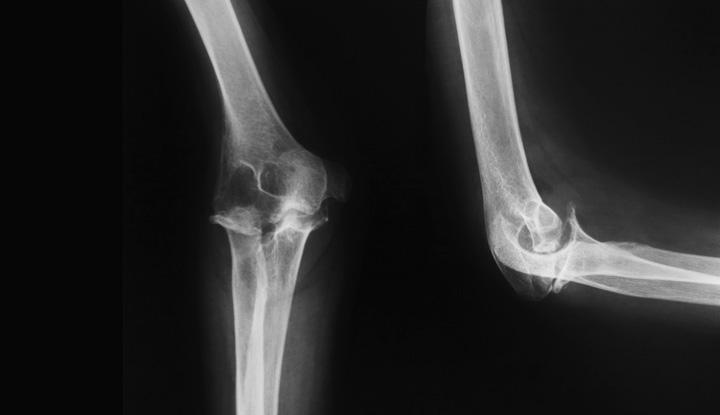

An elbow X-ray is a medical test that produces an image of the inside of your elbow. The image displays the inner structure (anatomy) of your elbow in black and white. An elbow X-ray shows your soft tissues and elbow bones. Your elbow bones include the upper bone of your elbow joint (humerus) and the lower bones of your elbow joint (radius and ulna). Your healthcare provider will use an elbow X-ray to diagnose and treat health and medical conditions in your elbow.

X-rays use a type of radiation called electromagnetic waves to create a picture of the inside of your body. Healthcare providers use X-rays more often than any other kind of medical imaging. X-rays send a beam of radiation through your body. Calcium in your bones absorbs more radiation, so your bones appear white. Soft tissues absorb less radiation, so they appear in various shades of gray. Air appears black.

A normal elbow X-ray includes at least three images. Your technologist will return to reposition your elbow as needed. One image will be taken from the front (anteroposterior view), one image will be taken from the side (lateral view) and one image will be taken at an angle (oblique view). If you’re in any pain, let your technologist know so they can help assist you through the test.